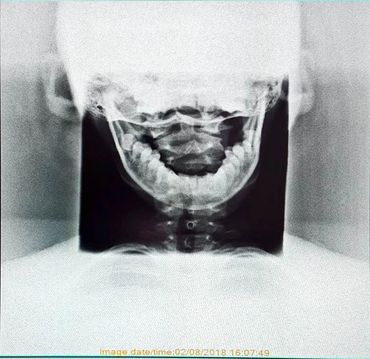

An 11 year old patient came into the clinic referred by her mother. The patient was complaining of headaches and an inability to focus at school after sustaining a blow to their head in a soccer game. Upon examination and an x-ray of their cervical spine (neck) we observed a shift in position of their first vertebra corresponding to the side of impact. After a course of chiropractic treatment and acupuncture the patient's symptoms reduced. Both the patient and their family are pleased with the results and with the patient's restored ability to function optimally at school and with their daily activities!